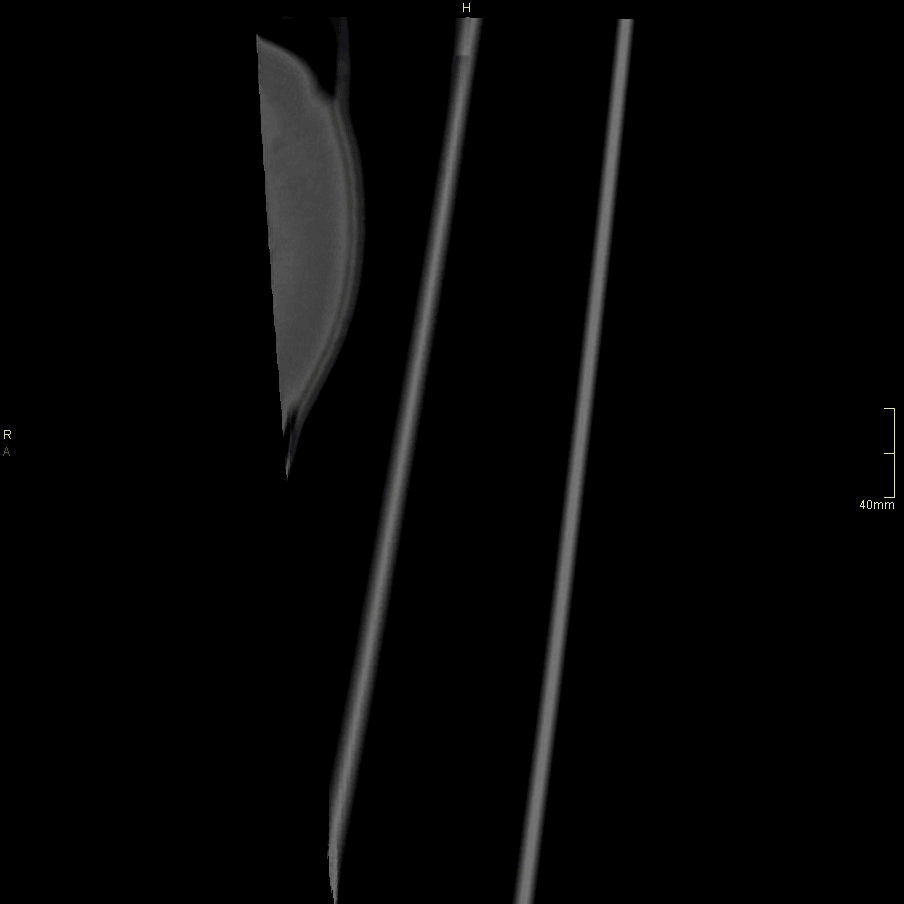

CT Humerus Contrast- Soft tissue window (coronal)

CT Humerus Contrast- Soft tissue window (sagittal)

CT Humerus Non Contrast- Bone window (coronal)

CT Humerus Non Contrast- Bone window (sagittal)